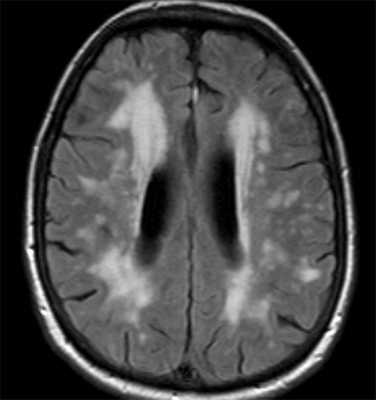

- МРТ головного мозга. Выявляет расширение III желудочка, атрофические изменения среднего мозга, базальных ганглиев, премоторных зон лобной коры и височных областей. Позволяет исключить внутримозговую опухоль, энцефалит, рассеянный склероз, инсульт.

Синдромы Паркинсона включают группу заболеваний, близких по клинике к болезни Паркинсона. К синдромам Паркинсона относится быстро прогрессирующая деменция с тельцами Леви . При МРТ головного мозга низкий сигнал наблюдается не только от компактной части черного вещества, но и от скорлупы, которая становится даже темнее бледного шара. При оливопонтоцеребеллярной атрофии на сагиттальных МРТ головного мозга видно уменьшение объема моста и мозжечка. При прогрессирующем надъядерном параличе обнаруживается атрофия пластины четверохолмия. Описаны характерные симптомы при МРТ - «пингвина», «Микки Мауса» и другие, смысл которых заключается в описании признаков атрофии.

- коэффициент средний мозг-мост в норме 0,24, а при прогрессирующем надъядерном параличе становится меньше 0,12.

- Индекс паркинсонизма - отношение ширины верхней ножки мозжечка в корональной плоскости к площади среднего мозга в средней сагиттальной плоскости умноженной на отношение ширины средней ножки мозжечка к ширине верхней ножки мозжечка - больше 13,55 свидетельствует в пользу паркинсонических синдромов. При МРТ выявляется атрофия хвостатых ядер с вторичным расширением передних рогов; атрофия скорлупы и коры лобных долей. Отношение ширины передних рогов к расстоянию между хвостатыми ядрами (по их краям), измеряемое в поперечной плоскости уменьшается с 2,2-2,6 до значений близких к 1,0. Другой коэффициент - расстояние между хвостатыми ядрами (между их головками к ширине черепа по внутренним пластинкам) - увеличивается (в норме 0,09-0,12).При МРТ головного мозга выявляется диффузная атрофия мозга, расширение периваскулярных пространств Вирхова- Робена и лейкоараиоз. Последний является следствием стеноза и окклюзии глубоких вен мозга. На Т2-зависимых МРТ изображениях лейкоараиоз выглядит как небольшие очаги гиперинтенсивности. В целом эти признаки неспецифические и отражают старение мозга. При МРТ головного мозга на томограммах обоих типов взвешенности обнаруживается повышенный сигнал от моста и покрышки мозжечка. Типично изменение сигнала от периферии моста. В отличии от опухолей при МРТ нет отека и масс-эффекта. Самые ранние проявления обнаруживаются на диффузионное-взвешенных МРТ головного мозга, примерно через 24 часа от начала тетрапареза.